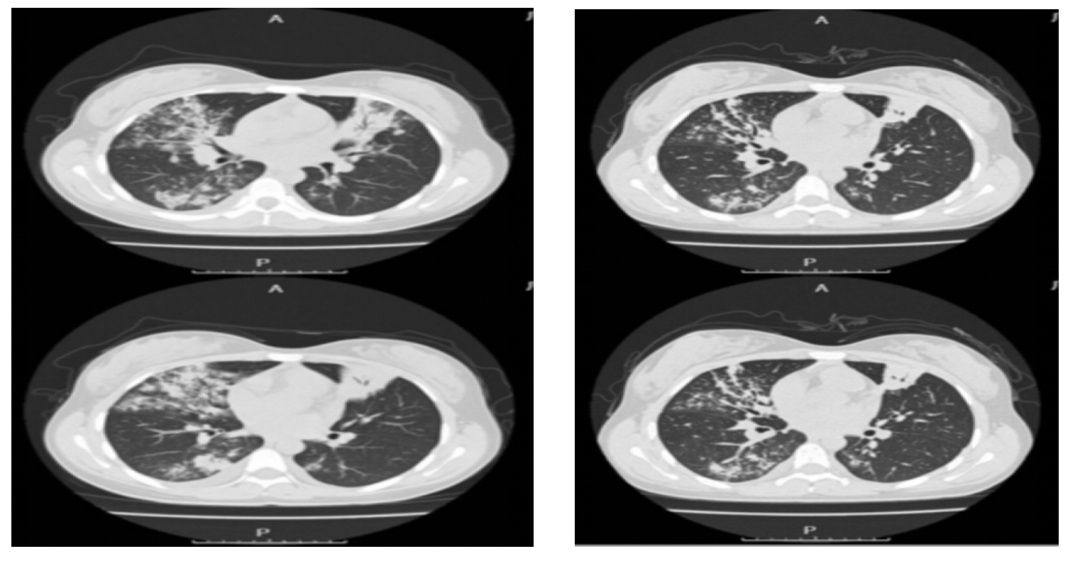

左图:入院时胸部CT示双肺多发感染,部分实变影;右图:治疗8天后,患者肺部渗出、实变比之前吸收减少。在小美退热后,护师又通过雷火灸等中医特色疗法,有效缓解了头晕、恶心呕吐、食欲差等症状,临床症状明显改善,病情好转,住院8天后已出院。“一般来说,鹦鹉热衣原体肺炎疗程一般为10至14天,但是患者症状大部分好转,复查指标显示没有其他并发症,出院后继续口服药物即可。住院时间明显缩短了,也减少了经济负担。”孔祥照说。